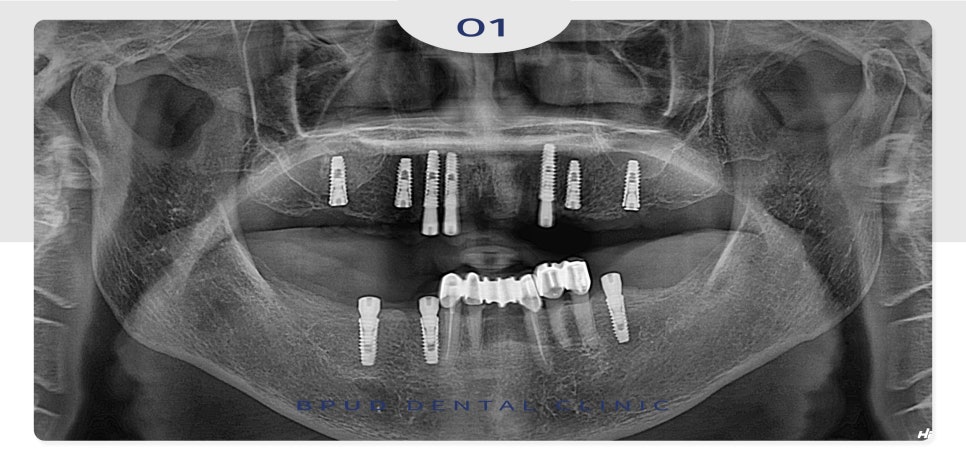

23.04.15

먼저 위쪽에 남아있던 치아들은

심한 우식과 치주염으로 상태가 좋지 않아

전체 발치 후 7개의 임플란트를 식립하였고

아래쪽은 남아있는 치아를 보존하여

필요한 만큼의 임플란트만 식립을 하였습니다.

그와 동시에, 위쪽은 부족한 부분의 뼈이식을 위해

오른쪽은 측방 접근법을 통한 상악동 거상술,

왼쪽은 치조정 접근법을 통한 거상술을 시행하였습니다.

상악동 거상술은 부족한 잇몸뼈 이식을 위해

상악동 막을 들어 올리고 그 공간에 뼈이식재를

삽입하여 임플란트가 안정적으로 고정될 수 있도록

해주는 술식을 말하는데요.

부평치과 치료법은 크게 두 가지로 나누어져,

먼저 치조정 접근법은 잇몸을 통해 상악동에

접근하여 상악동막을 들어 올리고

뼈이식을 하는 방법으로

비교적 적은 양의 이식이 필요한 경우 사용되어

상대적으로 간단하고 회복이 빠른 편입니다.

측방 접근법은 위턱뼈의 측면에 작은 창을 만들어

상악동막을 들어 올리고 뼈를 이식하는 방법으로

더 많은 양의 뼈이식이 필요하거나 직접적인 접근이

어려운 경우에 적용되어 넓은 뼈를 이식할 수 있다는

장점이 있지만 수술 과정이 복잡하고

시간이 오래 걸릴 수 있습니다.